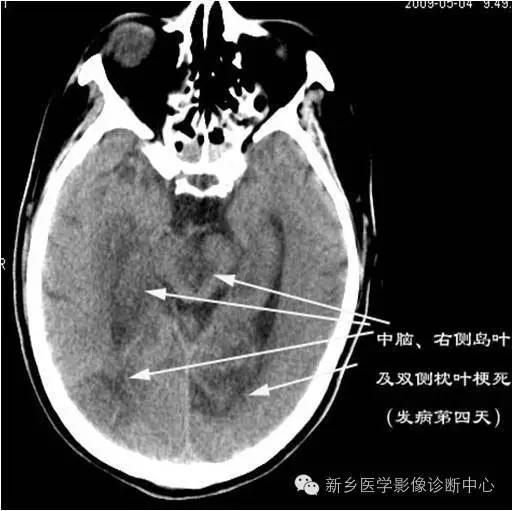

影像表现

影像表现:

脑部CT、MRI检查,显示累及基底动脉尖部5条血管供血区的2个以上梗死灶。常见部位依次为:丘脑、中脑、小脑、枕叶、颞叶等。

最大特征为双侧丘脑梗死,病灶位于丘脑中心部位,成蝶形、对称性分布。